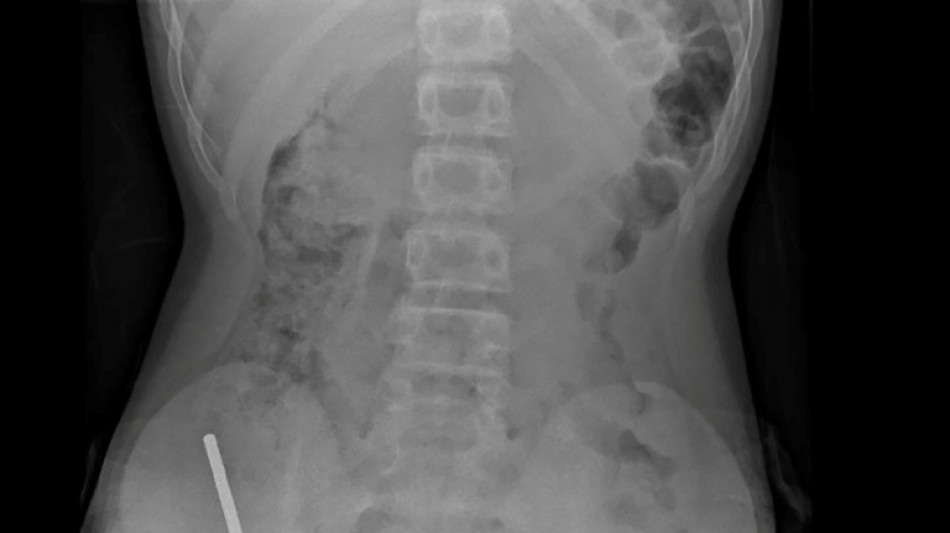

Nouvelle-Zélande: un adolescent opéré après avoir ingéré près de 100 aimants achetés sur Temu / Photo: Handout - NEW ZEALAND MEDICAL JOURNAL (NZMDJ)/AFP

En Nouvelle-Zélande, un adolescent de 13 ans s'est vu retirer plusieurs parties nécrosées de ses intestins après avoir avalé près d'une centaine d'aimants achetés en ligne sur le site Temu, a rapporté vendredi une revue médicale.

"Il avoué avoir ingéré entre 80 et 100 aimants puissants au néodyme, de 5x2mm environ, une semaine plus tôt", indique un rapport des médecins de l'hôpital de cet hôpital, publié dans le New Zealand Medical Journal (NZMJ).

Les médecins ont déclaré que la pression exercée par les aimants avait provoqué une nécrose dans quatre zones de l'intestin grêle et du gros intestin du garçon.